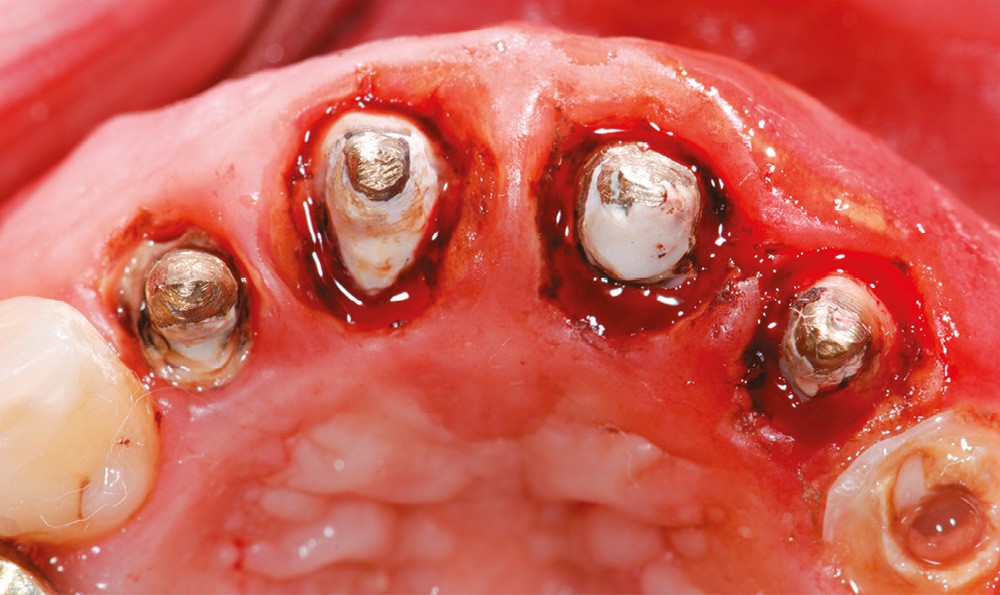

1 – Le système d’attache d’une dent est composé de l’os alvéolaire, du ligament alvéolo-dentaire et de l’attache épithélio-conjonctive ou attache supra-crestale. L’attache supra-crestale, anciennement confondue avec l’espace biologique, est un espace d’environ 2 mm [1] occupé par l’attache conjonctive (1 mm) et l’attache épithéliale (1 mm). Il est normalement visible à la radiographie rétro-alvéolaire entre le sommet de la crête osseuse et la jonction émail-cément. Comme une dent possède naturellement un sulcus, certains auteurs estiment qu’il convient d’y ajouter au moins 1 mm de sulcus libre de toute structure prothétique [2]. On peut donc considérer l’espace biologique comme un « espace clinique sanctuarisé » de 3 mm au sommet de la crête osseuse alvéolaire, nécessaire à la santé et à la stabilité parodontale. La violation de l’espace biologique génère un traumatisme parodontal aboutissant à des récessions gingivales ou des gingivites prothétiques (fig. 1a-b).

Même en l’absence de restauration, l’espace biologique n’est parfois naturellement pas correctement établi sur la dent. Ce phénomène est couramment décrit comme une éruption passive retardée. Elle peut être une indication d’élongation coronaire esthétique afin de rétablir la couronne clinique dans son intégralité (fig. 2a-c).